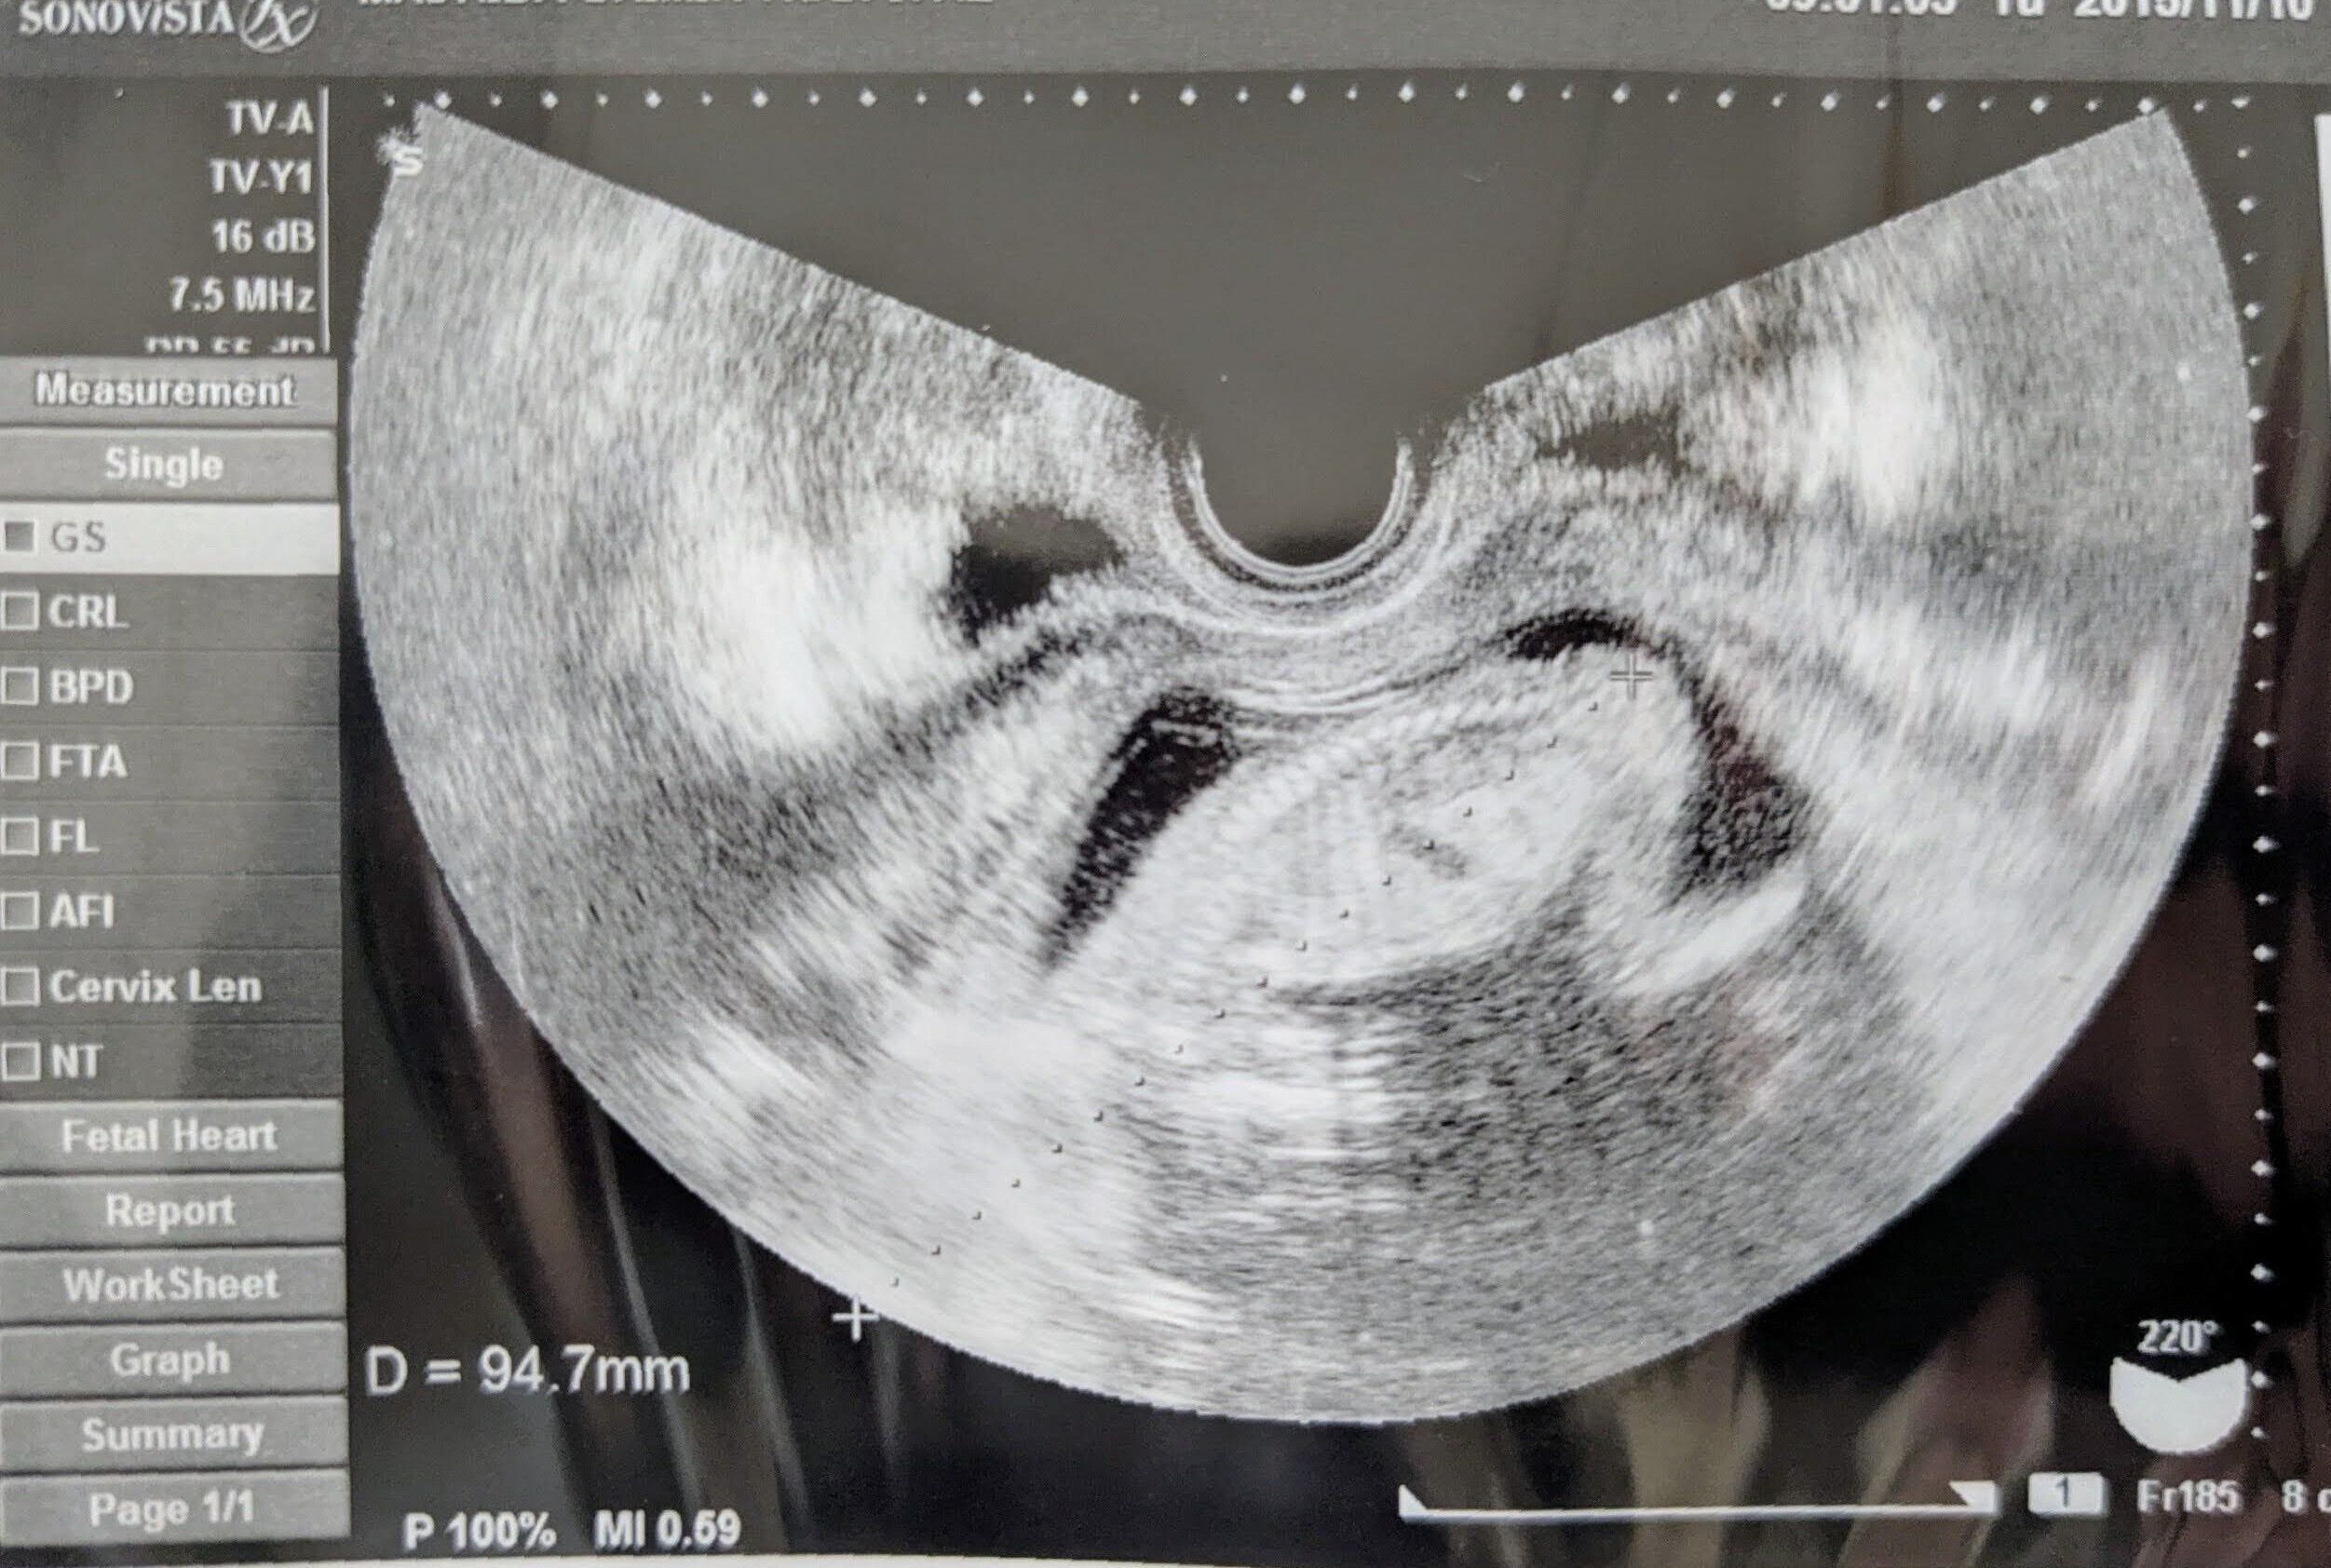

年の瀬間近の12月28日、妊娠5カ月(19週目)に、初めておなかの上からのエコー検査を。夫婦2人で病院に行き、一緒にモニターを見ました。

「最初のうちは『小顔だね~』とか言ってはしゃいでいたのですが、先生がおしりのあたりを何度も何度も確認していることに気づきました。私たちも気をつけて見てみると、おしりのあたりに丸い空洞のようはものが・・・。

あれは何???と思っていたところ、『脊椎がうまく閉じず、中の神経や髄液が外に出てきてしまう奇形の可能性がある』という、衝撃的な言葉が医師の口から飛び出したんです。

「おしりのあたりのふくらみを、前回よりもさらに詳しく調べていました。心臓、そのほかの臓器、頭の中もじっくり見ているのがわかりました。その結果、二分脊椎と診断され、水頭症やキアリ奇形の可能性があることも告げられました」(香織さん)

2月頭、妊娠7カ月(26週目)に国立成育医療研究センターを初受診。じっくりエコー検査をしたあと、今後のことについて説明を受け、2週間後の健診では胎児MRIを受けました。

「脊椎が開いている幹部は、比較的低い位置だとわかりました。低い位置ほど独立歩行の可能性が高まるそうなので、少しだけ希望が見えました。でも、排せつ障害や下肢まひによる歩行困難はあるそう。水頭症やキアリ奇形の可能性も消えていません。